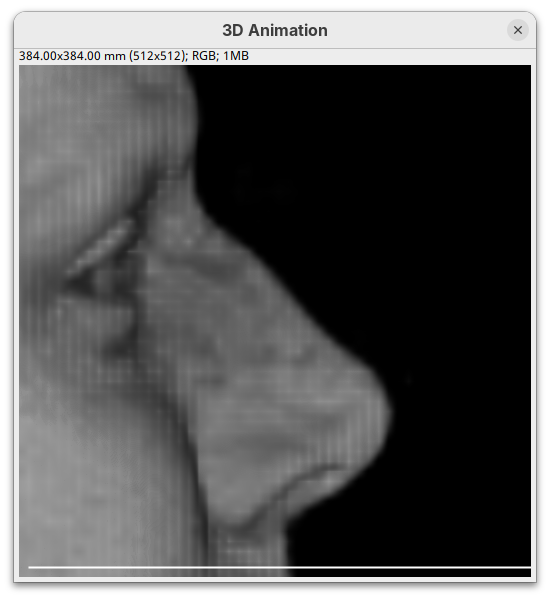

3D Project

This is a simple tool to quickly generate a 3D animation (e.g., 360-degree rotation) from an image stack. There are basic parameters for adjusting the rendering, like projection method and opacity, and for controlling the animation. There’s only a bit of documentation. To try:

- Go to

Image>Stacks>3D Project...and clickOKto generate a basic animation.

As noticeable above, 3D Project doesn’t do so well with our MRI dataset. However, it works OK for fluorescent microscopy images, so I encourage you to try with other datasets in the future.